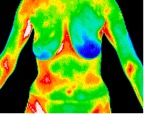

6- Car accident, fractured sternum.jp2

Car accident, fractured sternum